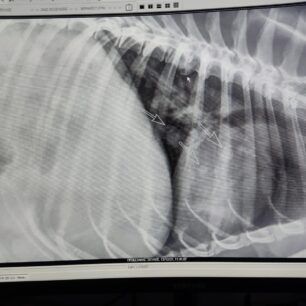

Οι ακτινογραφίες έδειξαν τους όγκους παντού στο σώμα του ζώου…